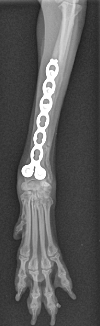

Fracture Salter-Harris sur un chaton Européen de 10 mois

Spike, chaton européen mâle de 10 mois, a été présenté en consultation pour boiterie du membre postérieur droit à la suite d'une chute depuis le 1er étage.

A la radiographie, une fracture de type Salter-harris 1 est diagnostiquée, avec déplacement de l'about discal.

Une réduction de la fracture par pose de 2 broches en croix a été réalisée.